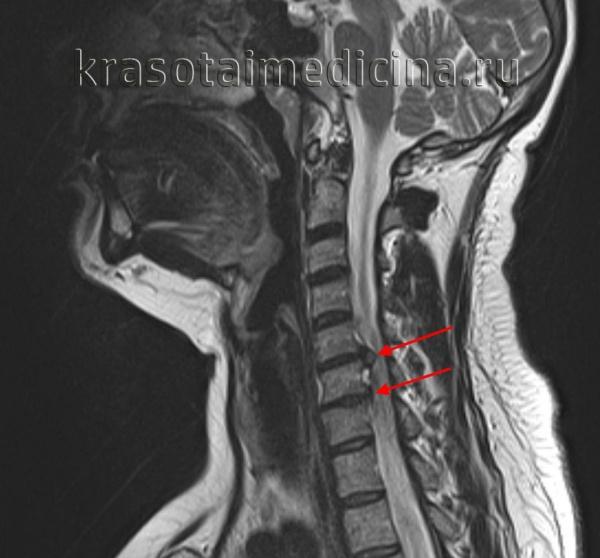

- Диагностика: МРТ, КТ, рентгенография для определения степени повреждения.

Как правильно поставить диагноз?

Врач может назначить одно из следующих инструментальных исследований:

Магнитно-резонансная томография (МРТ) — это безболезненное и неинвазивное исследование, с помощью которого благодаря магнитному полю получают детализированные изображения всех структур тела, включая мягкие ткани. МРТ позволяет визуализировать нервы и межпозвоночные диски, что невозможно с помощью рентгена.

Данное исследование позволяет врачу хорошо рассмотреть все структуры срез за срезом (снимки проводят в виде «срезов» через 1-2 см, как будто рассматривают нарезанный хлеб кусок за куском). Снимки можно делать сверху вниз, сбоку, наискосок. Можно применить внутривенный контраст, или обойтись без него. МРТ показывает, какой именно диск поврежден и есть ли защемление нерва. Кроме того, врач может увидеть костные разрастания, опухоли спинного мозга, абсцессы.

- Магнитно-резонансная томография;

Наиболее полное представление о состоянии хрящевой ткани позвоночника дает МРТ, позволяя получить послойные изображения и точно оценить расположение и размеры выпячивания.